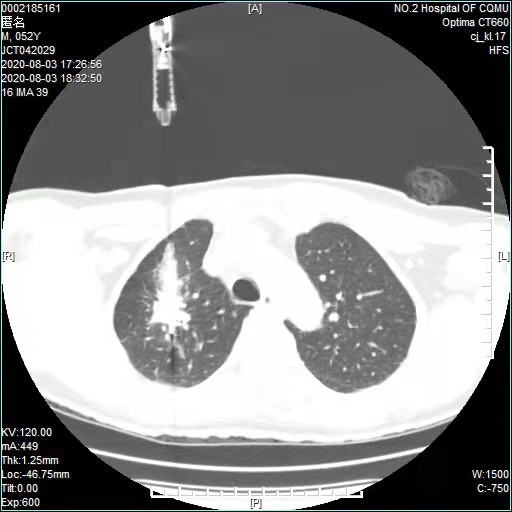

经过充分的术前准备、评估,2020年8月初,郑先生接受了射频消融微创治疗。术中,江德鹏教授在患者体表定位后,将单极射频肿瘤消融电极针,准确置入病灶中心部位,然后开始射频消融治疗。在治疗过程中,又适时调整穿刺方向及深度,密切观察患者的反应及生命体征。

(术中)

整个手术耗时1小时左右,因不必全身麻醉,患者术中未诉任何疼痛。消融完毕行胸部CT扫描,达到了完全消融的影像学特征,未见明显气胸和出血等情况。神奇的是,术后第二天,郑先生的一些胸部不适症状就消失了,目前,郑先生在医生的指导下规范治疗,疾病没有进展。